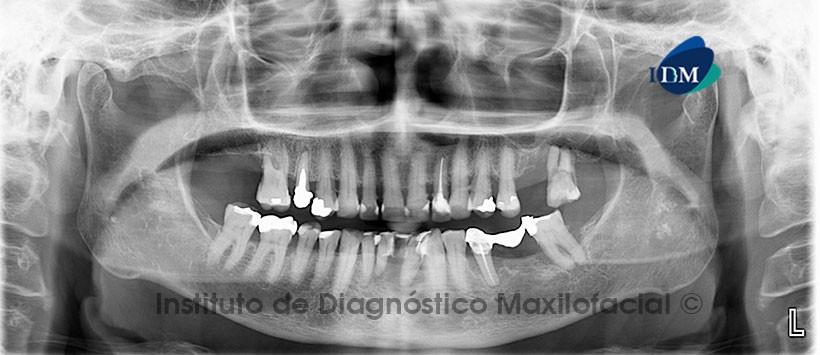

Paciente femenino de 76 años de edad es referido al Instituto de Diagnóstico Maxilofacial (IDM) para evaluación general por presentar enfemedad periodontal avanzada.

A la evaluación de la radiografía panorámica se aprecia reabsorción ósea alveolar moderada a severa con presencia de defectos angulares a nivel de las piezas 2.7, 3.7, 3.5, 3.2 y 4.1. Así mismo como hallazgo radiográfico se aprecia multiples imágenes radiopacas de límites definidos y bordes irregulares proyectadas sobre la rama mandibular de ambos lados. (Figura 1)